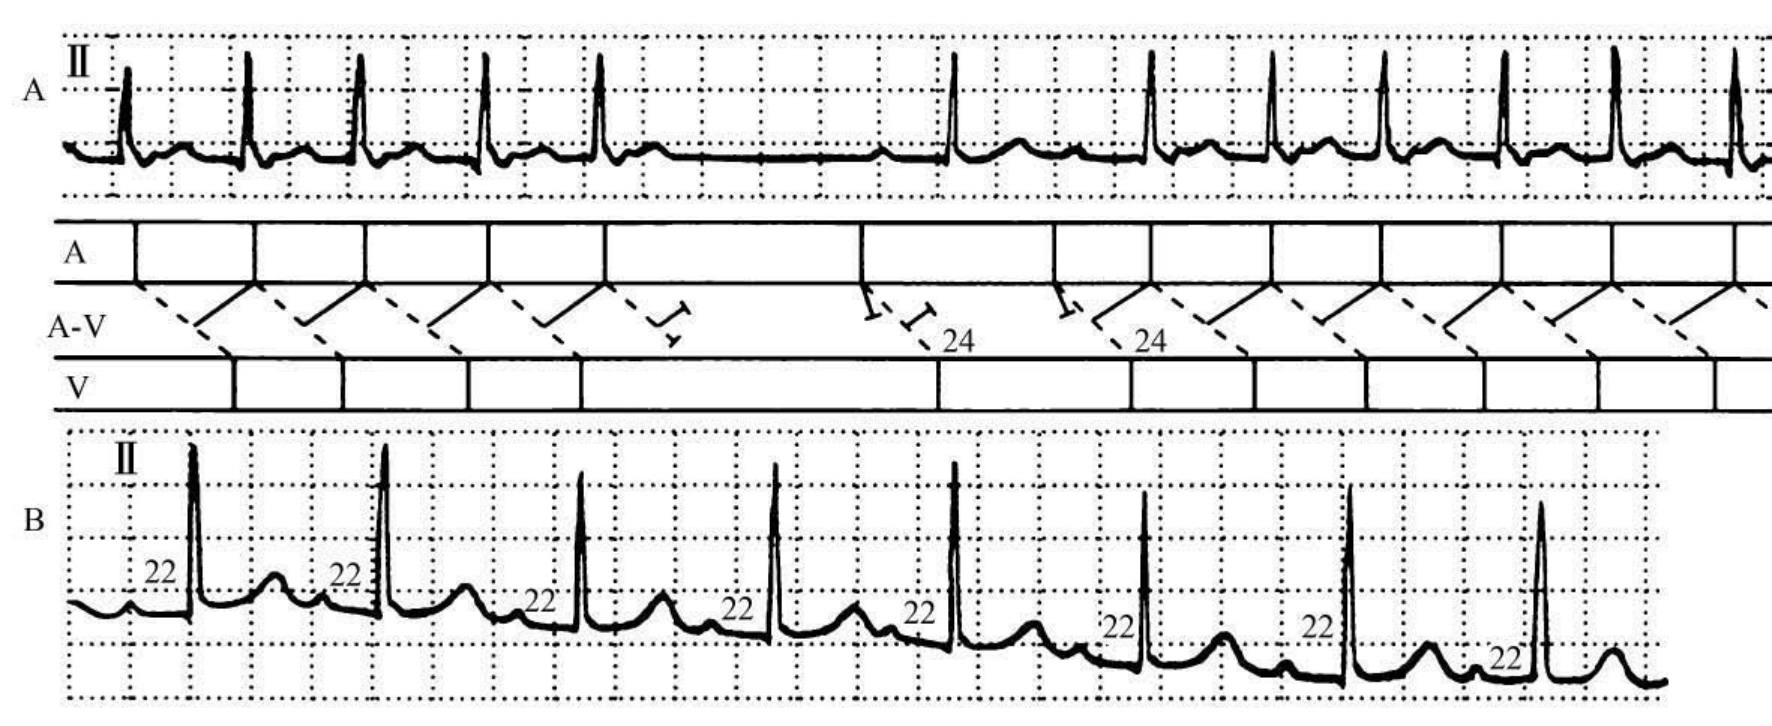

图37-14 慢—快型房室结内折返性心动过速

患者女孩,12岁,临床诊断:风湿性心肌炎。A图中段出现2个窦性P波,第2个P波直接诱发房室结内折返性心动过速(慢-快型)。心动过速时的P-R间期延长(0. 24s),而R-P间期约0.07s。B图是第5天复查心电图Ⅱ导联,P-R间期为0.22s,窦性心律的频率为93次/min,仍为一度房室阻滞